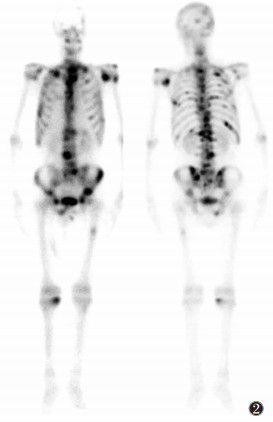

90%以上的骨转移病灶为多发性,约10%为单个转移灶。骨转移瘤的显像特征为多发、不规则的放射性“热”区,以脊椎和肋骨最常见,其次是骨盆、四肢骨近端、胸骨和颅骨,四肢骨远端转移较少见。少数患者呈“冷”区或“冷”区与“热”区并存。骨转移瘤在初期反应阶段,当成骨反应变化达到10%~20%时,呈异常“热”区表现。

![]() |

| 图 1 正常骨显像前位及后位全身图像 |